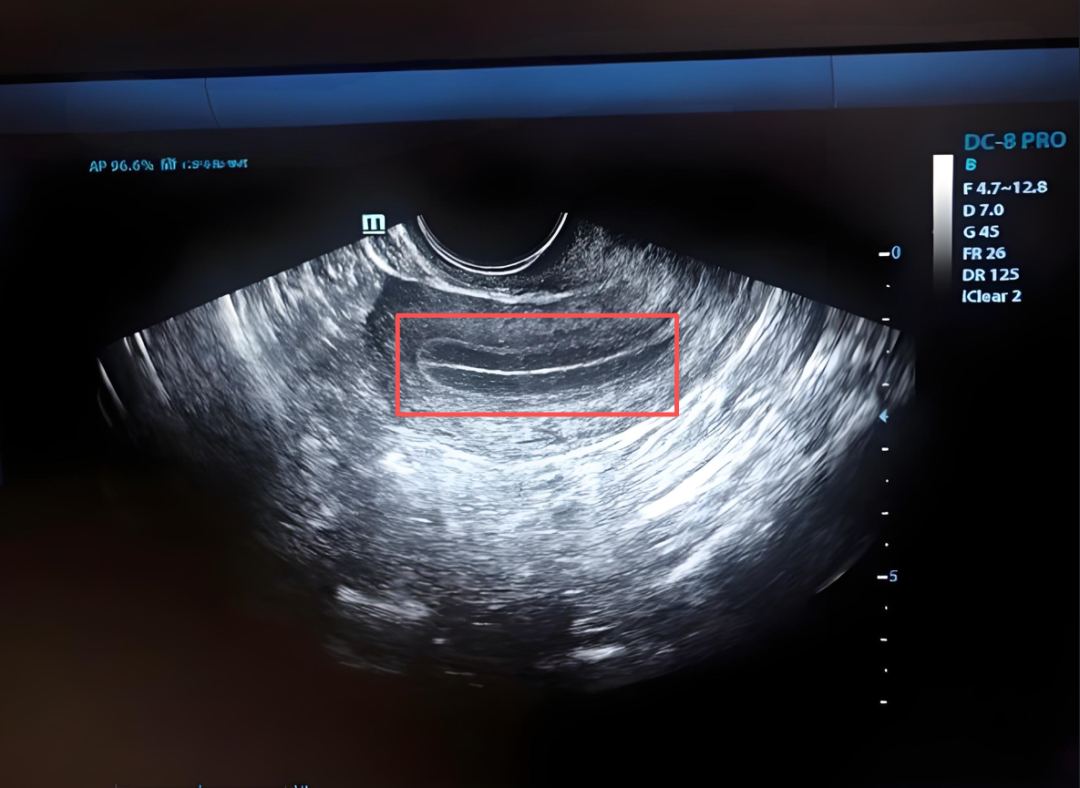

什么是内膜三线征

内膜三线征,也叫 “三线型内膜” ,是经阴道(或腹部)B超检查时,对子宫内膜形态的一种描述。在B超图像上,可以看到三条平行的亮线。

上线(前壁的线)= 前壁的基底层与子宫肌层的交界

下线(后壁的线)= 后壁的基底层与子宫肌层的交界

中间线 = 前壁与后壁的功能层在子宫腔中的交界面(宫腔线)